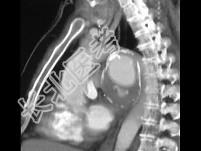

- 单项选择题患者60多岁,男性, 胸部不适加重,最可能的诊断为 ( )

A、食管癌

B、肺癌

C、主动脉瘤破裂

D、淋巴瘤

E、以上都不是